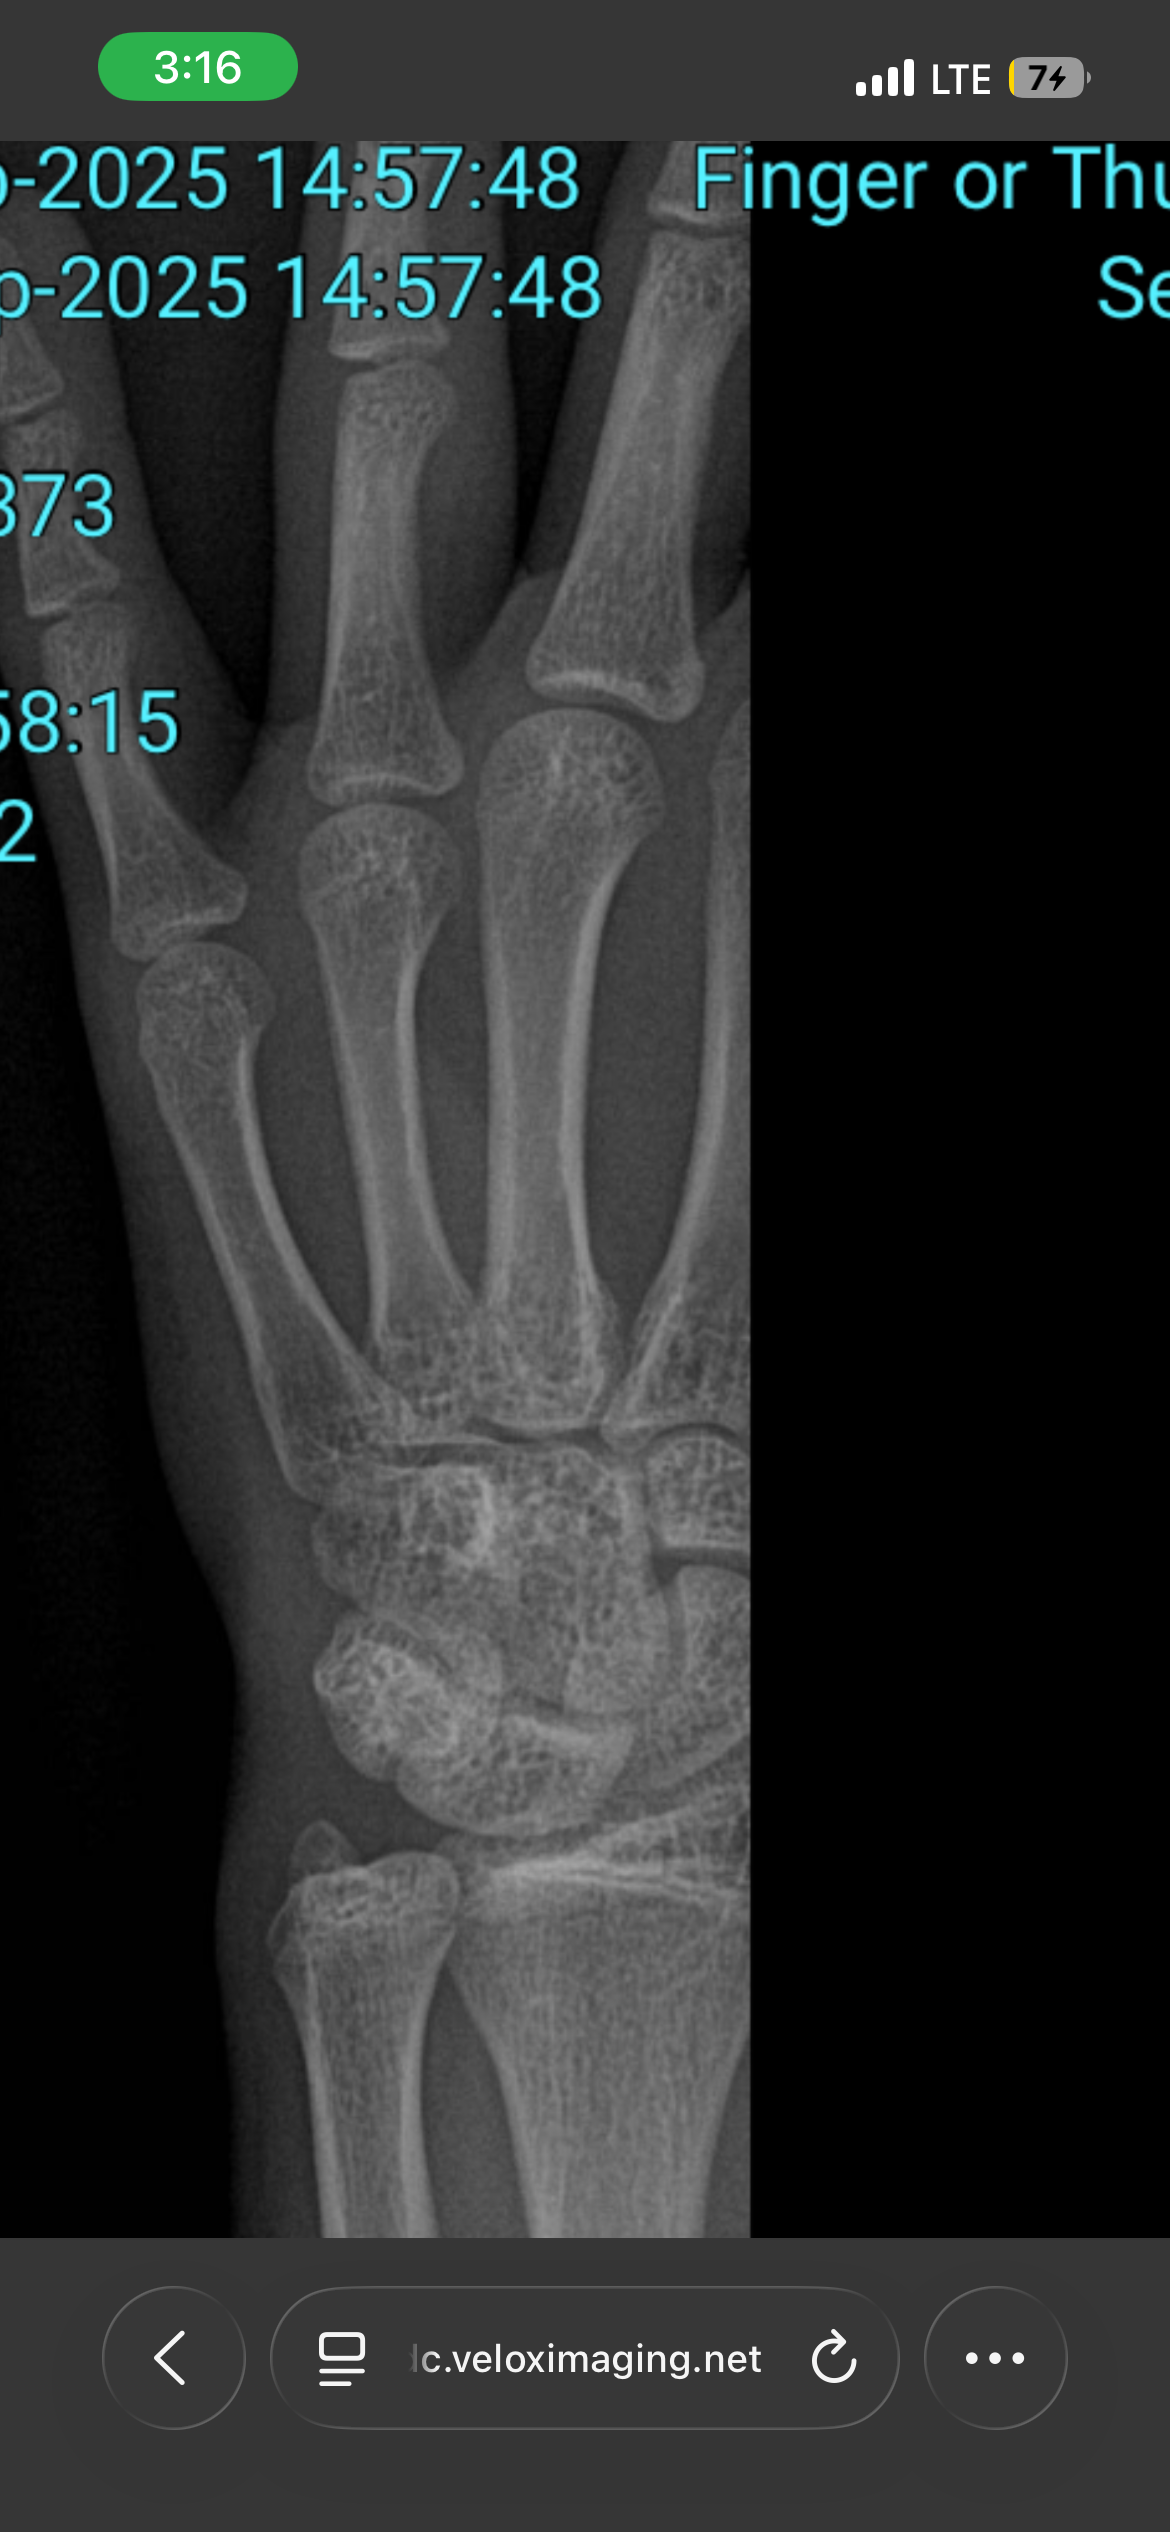

are my plates open????

im 5,4 too i think im cooked

r they like open or not?